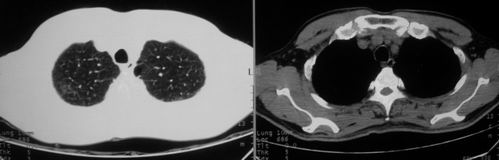

男,62岁,咳血两天。无其他不适。

右肺上叶浅淡密度增高影,考虑炎性病变

片状磨玻璃影,考虑肺泡出血可能性大,其他不排除,建议hrct

右上磨玻璃样密度影,考虑就是个肺泡出血,别的没有

病灶呈“磨玻璃影”,较薄,周围无卫星灶,很难一口说是肺结核,建议积极治疗后,短期复查!(支持考虑:肺泡出血!)

右肺上叶可见多发磨玻璃状影,符合肺泡内出血表现,严格意义上讲应该是肺泡内积血。引起出血的原因很多,不一定非得结核所致。